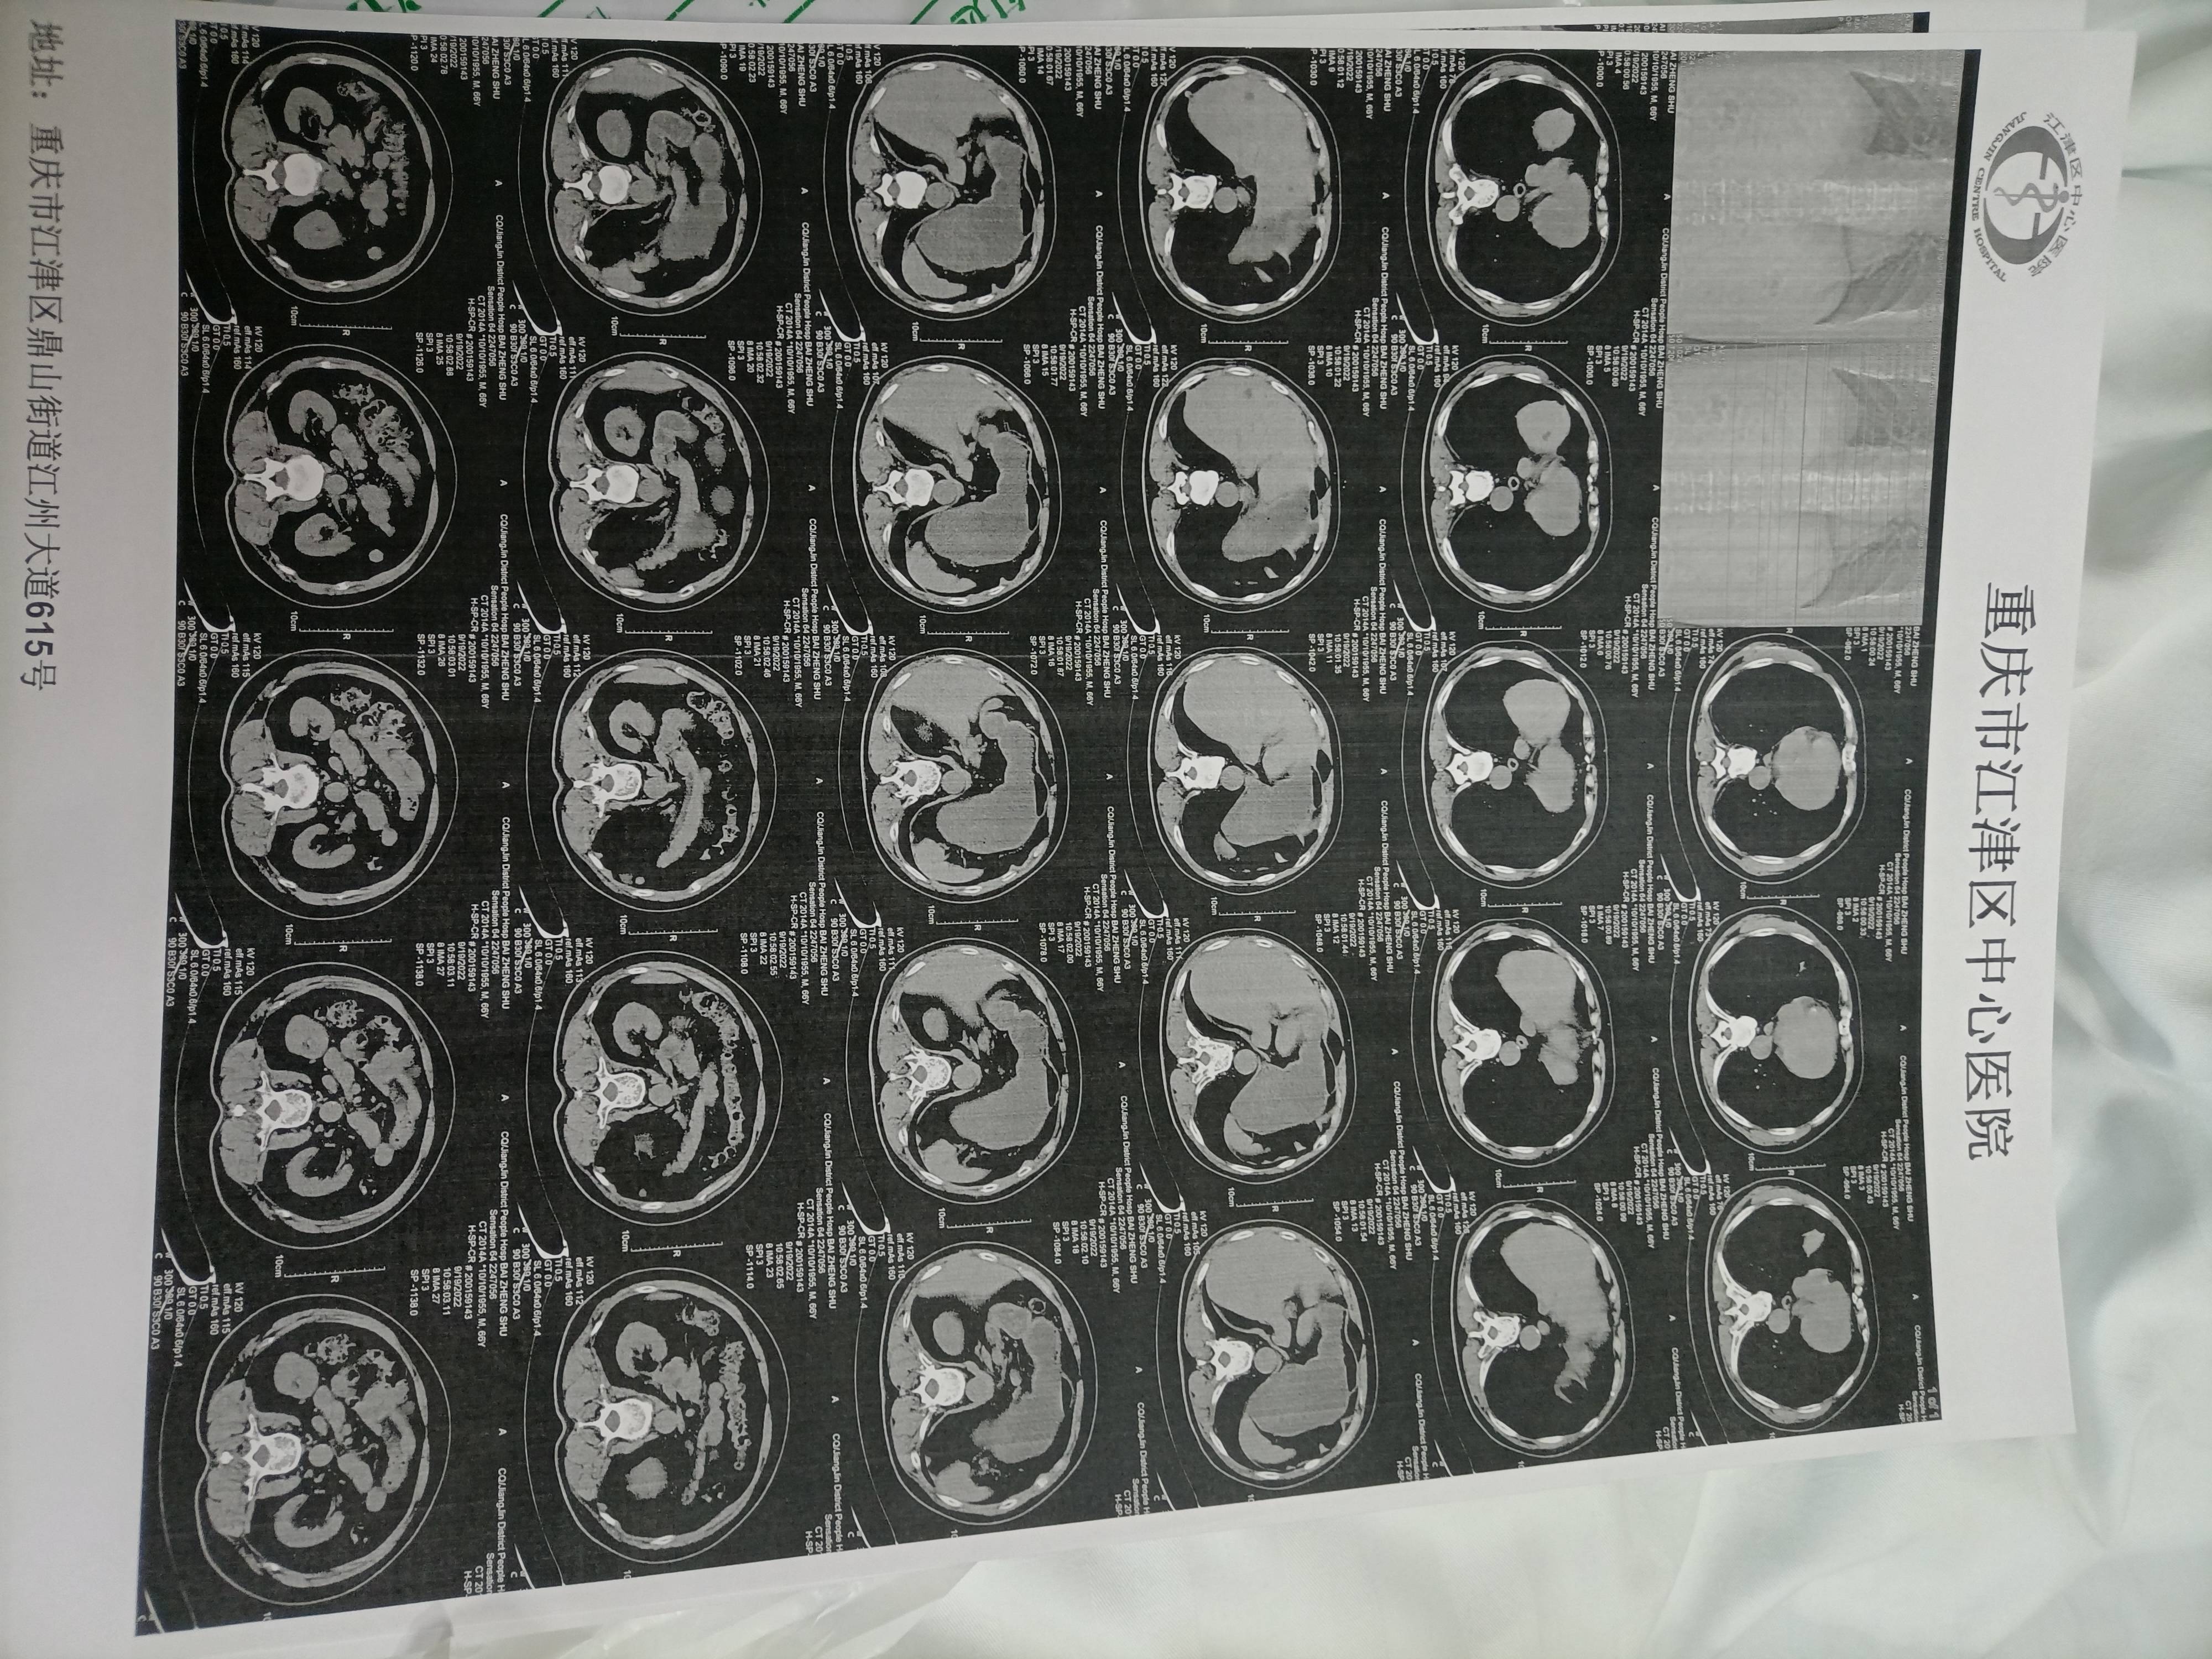

这个怎么看哪里还有结节?

不是专业人士看不出。。。平常人士就看报告就好。有结节会说明

这些临床医生都不看,只有电视剧里的医生才看。